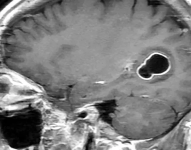

Curiosidades El hombre con migrañas al que médicos en EE.UU. le encontraron larvas en el cerebro por comer carne de cerdo poco cocida